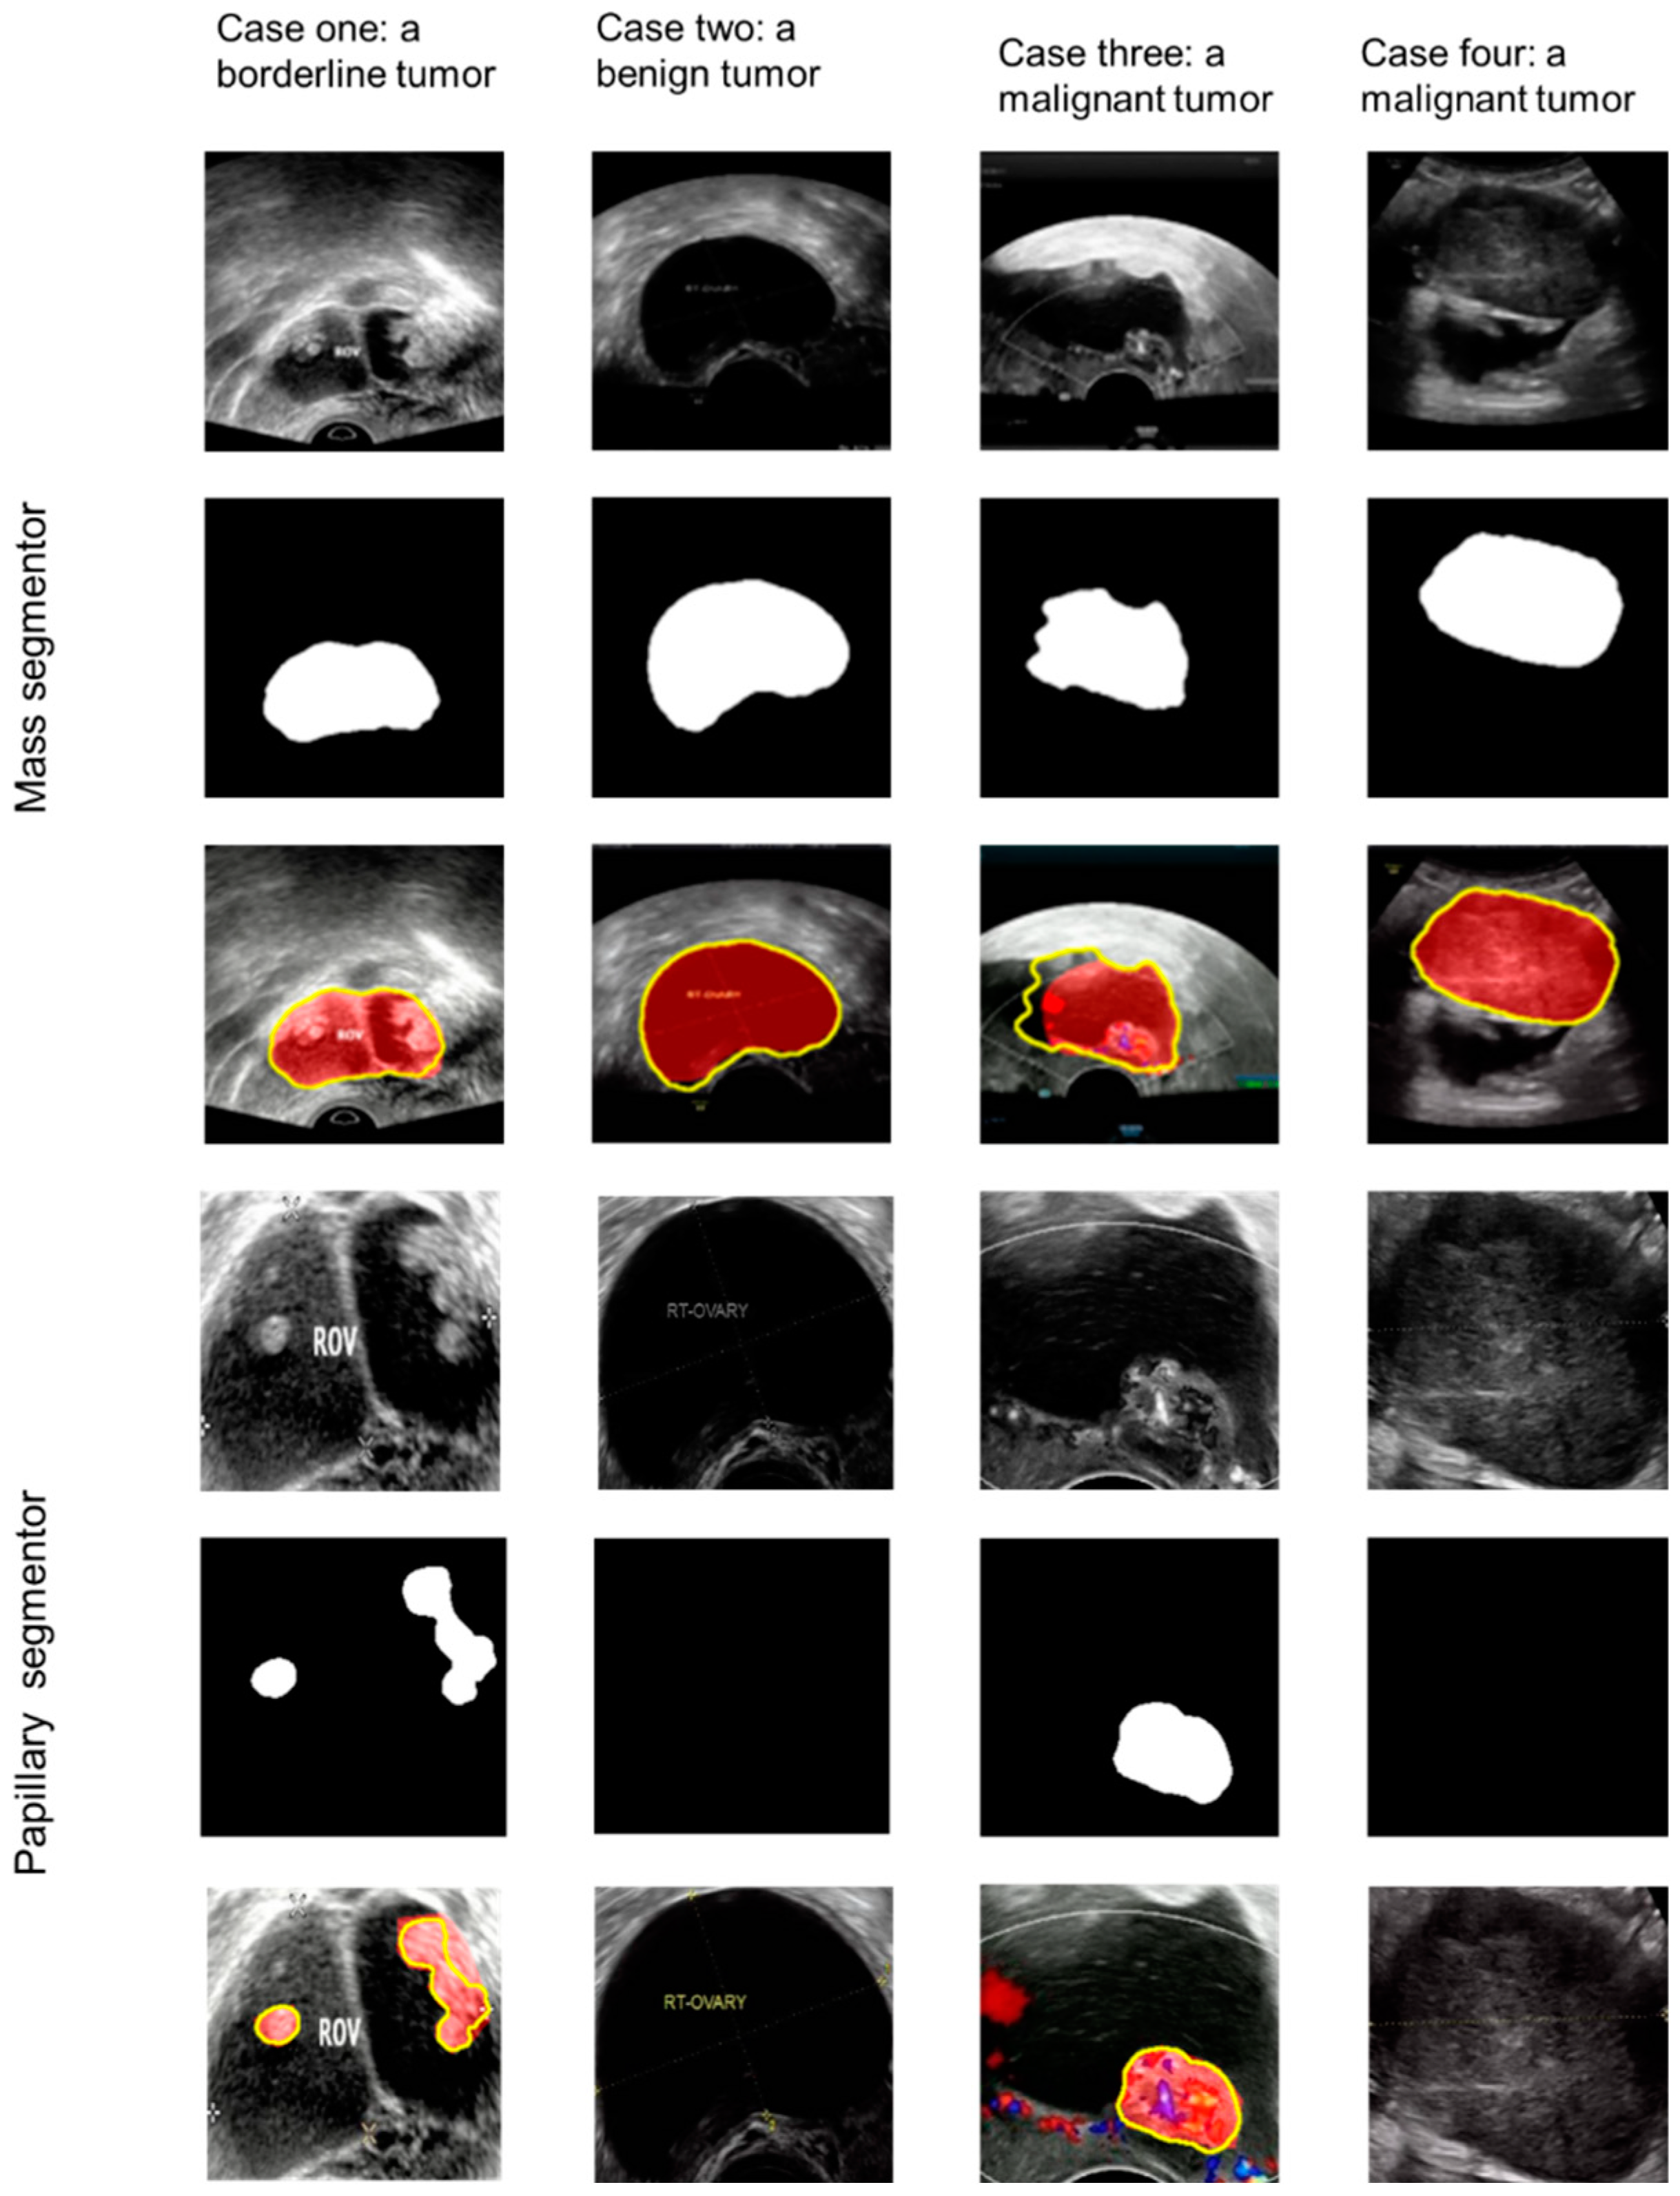

2.3. Annotation and Framework

3.2. Papillary Projections